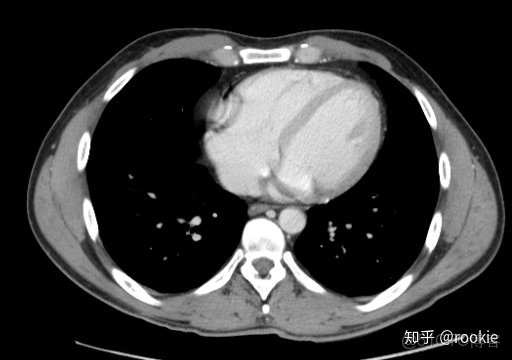

縱隔窗口窗口設置: (W:500,L:50)優點: 這些設置在本質上與軟組織設置或腹部設置相似,並進行了微調,以儘可能清晰地顯示出縱隔病理。

CLAHE算法增強局部對比度的X光圖像增強效果對比_#python 計算對比度_13

縱隔窗與腹部或軟組織窗相似,但稍作調整以顯示縱隔結構。

CTA窗口窗口設置: (W:600,L:170)或(W:650,L:225)優點: 在評估CT血管造影研究(或在血管中具有明顯對比的CT掃描的任何階段)時,此設置可用於嘗試清晰地觀察血管病變。它在提供目標血管信號的同時具有良好的平衡,而無需血管內的亮度過高會沖洗腔內病變。

CLAHE算法增強局部對比度的X光圖像增強效果對比_ico_14

此窗口用於在感興趣的血管中有相當大的對比度的情況下(例如CT血管造影)。